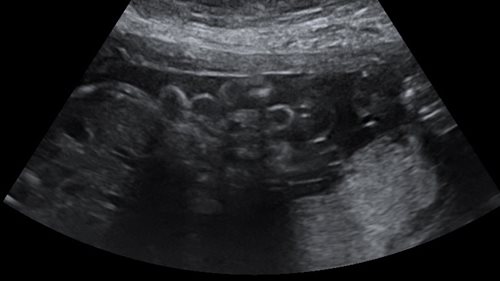

Cette pathologie rare (1/ 5000 naissances en Europe) est caractérisée par l’issue de viscères hors de l’abdomen foetal, sans sac, le plus souvent au bord latéral droit de l’ombilic. Il s’agit d’un défaut de la croissance embryonnaire et les malformations associées sont exceptionnelles. L’anse digestive herniée peut cependant être le siège d’une inflammation (périviscérite) plus ou moins importante ou présenter des complications parfois difficiles à suspecter avant la naissance. Celles-ci sont en relation probable avec un défaut de vascularisation mésentérique liée à l’étroitesse du collet et au contact des anses avec le liquide amniotique. Ainsi l’apparition au fil de la grossesse d’anses dilatées fait suspecter une obstruction dont le caractère « complet » correspond à une atrésie qui ne se rencontre que dans moins de 10 % des cas (figure 2). La mise en évidence d’un oligoamnios (quantité trop faible de liquide amniotique) ou d’un liquide amniotique trouble peut conduire à la réalisation prénatale d’amnio-infusions limitant le risque de lésions intestinales associées. Le laparoschisis étant régulièrement associé à un certain degré de prématurité, l’administration d’une corticothérapie à la maman de façon à « maturer » la fonction pulmonaire du foetus est régulièrement envisagée. Ce traitement par son caractère anti-inflammatoire puissant limiterait peut-être les lésions intestinales. Ces grossesses à risque font l’objet d’un suivi rapproché.

Figure 2